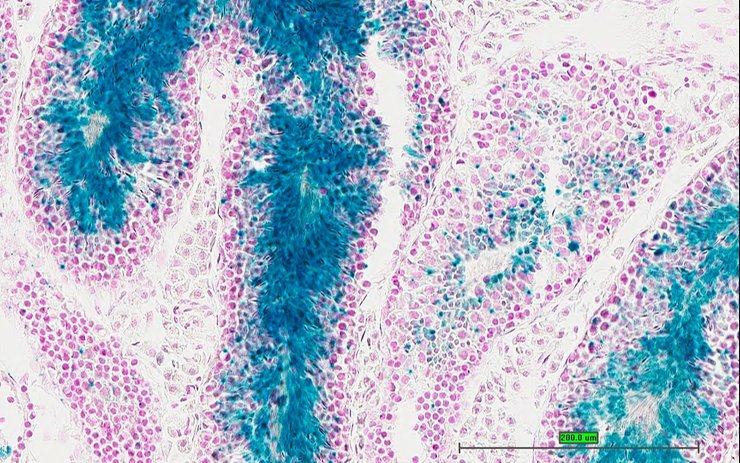

Specimen UC Davis_1870099: postnatal adult; Atf6btm1.1(KOMP)Vlcg/Atf6b+ (more )

Structure Level Pattern Image Note

TS28: colon Present UC Davis_1870099

Specimen UC Davis_1870100: postnatal adult; Atf6btm1.1(KOMP)Vlcg/Atf6b+ (more )

TS28: colon Present UC Davis_1870100

Specimen UC Davis_1870101: postnatal adult; Atf6btm1.1(KOMP)Vlcg/Atf6b+ (more )

TS28: cecum Present UC Davis_1870101

Specimen UC Davis_1870102: postnatal adult; Atf6btm1.1(KOMP)Vlcg/Atf6b+ (more )

TS28: cecum Present UC Davis_1870102

Specimen UC Davis_1870156: postnatal adult; Atf6btm1.1(KOMP)Vlcg/Atf6b+ (more )

TS28: colon Present UC Davis_1870156

Specimen UC Davis_1870157: postnatal adult; Atf6btm1.1(KOMP)Vlcg/Atf6b+ (more )

TS28: colon Present UC Davis_1870157

Specimen UC Davis_1870158: postnatal adult; Atf6btm1.1(KOMP)Vlcg/Atf6b+ (more )

TS28: colon Present UC Davis_1870158